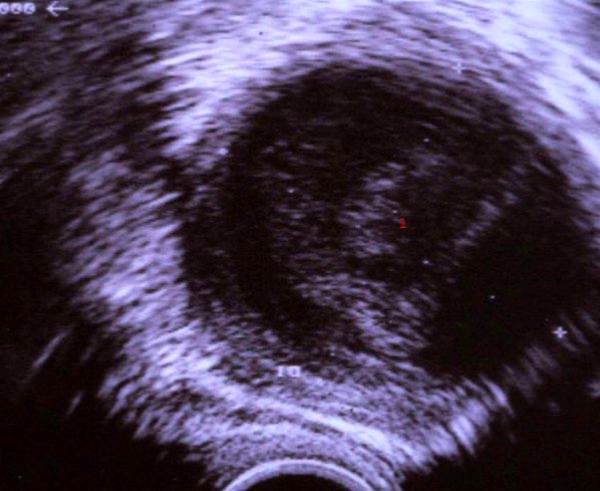

Ultralydskanning af byld på æggestok

Ansamling af betændelse i æggestokken påvist ved ultralydskanning